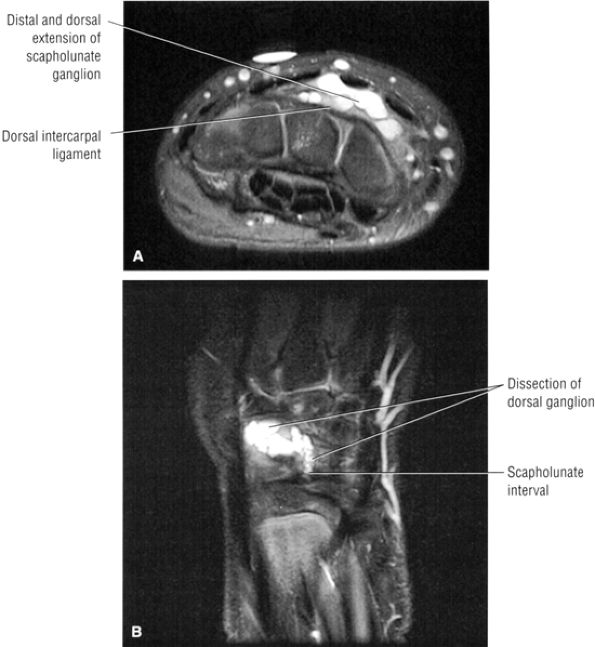

Associated dorsal ganglions in the dorsal or dorsal/membranous scapholunate ligament pathology (Fig. 10.100).